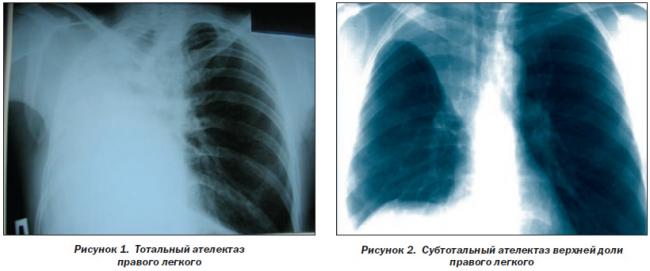

Помимо опроса и объективного осмотра, включающего перкуссию и аускультацию грудной клетки, проводят рентгенологическое исследование в двух положениях тела (в 2-х проекциях). Это основной метод обнаружения ателектазов легких.

На рентгеновских снимках выявляют следующие признаки, указывающие на спадение легочной ткани:

Однородное затемнение в области поражения. Размеры тени зависят от вида ателектаза: при долевом выявляется обширное затемнение, при сегментарном — в виде клина или треугольника, расположенного вершиной к корню легкого, дольковые ателектазы множественные и похожи на очаговую пневмонию. Дистензионный ателектаз расположен низко, около диафрагмы, имеет небольшие размеры и вид поперечных полос или темных дисков. Смещение органов: при компрессионном ателектазе смещение наблюдается в здоровую сторону, так как на стороне поражения давление больше, при обтурационном, наоборот – смещение будет в сторону ателектаза, так как на стороне поражения нарастает притягивающее отрицательное давление. Подъем купола диафрагмы – это видно по расположению печени.

Предварительным, рентгенологическим диагнозом является «синдром правой доли», при котором выявляется затемнение площади средней доли правого легкого.

Частое возникновение ателектаза правого легкого связано с анатомическими особенностями правого среднедолевого бронха: он узкий и длинный, поэтому часто происходит его перекрытие при патологическом процессе.